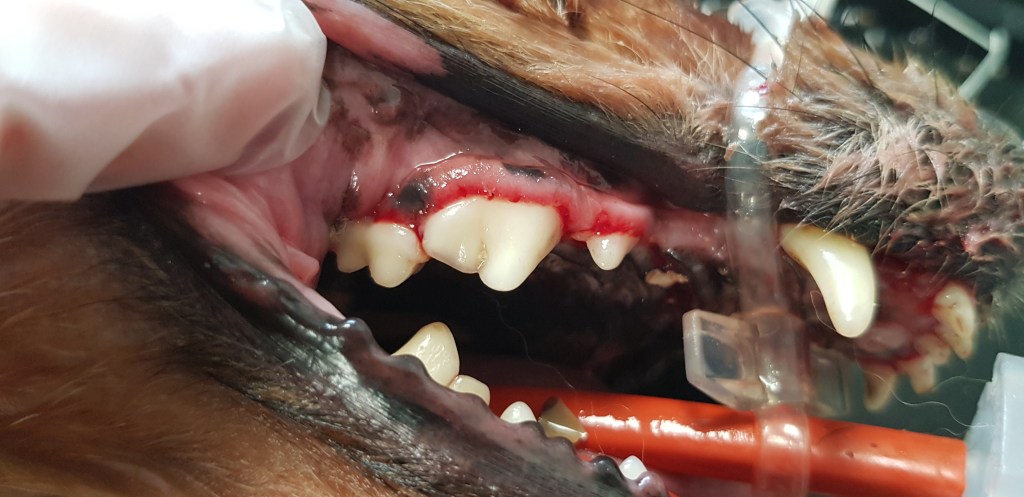

La mauvaise haleine de votre animal est souvent le premier signe d’une maladie bucco-dentaire. En l’absence de brossage, la plaque dentaire se dépose année après année sur les dents des chiens et chats. Peu à peu le tartre va s’insinuer sous les gencives et déchausser les dents qui s’infectent et finissent par tomber. Un détartrage régulier prévient ce risque et améliore la qualité de vie de votre animal.

Le tartre est un élément nocif pour votre animal. D’une part, il va peu à peu provoquer la chute des dents en les déchaussant. De plus, il provoque une irritation des gencives qui peut être source de douleur chez le chien et le chat. Enfin, les bactéries présentes dans la plaque dentaire peuvent passer dans le sang de votre animal et provoquer ensuite des lésions au niveau d’autres organes comme le cœur, le foie ou les poumons.